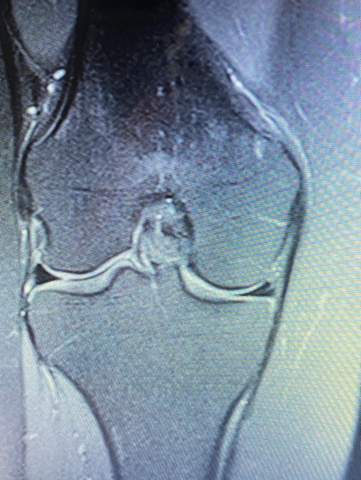

Und im Alter nagt Verschleiß an den Knorpelscheiben im Knie. Ein gesunder Meniskuszeigt sich im MRT als durchgängig schwarze Struktur MRT-Aufnahme bei Schmerzen im Knie. Zum besseren Verständnis des Krankheitsbilds Scheibenmeniskus trägt eine allgemein anerkannte Klassifikation der Variationen des lateralen Meniskus bei die Watanabe-Klassifikation.

Dabei wird das Weichteilgewebe der KnieBänder Menisken Muskeln etc hochauflösend in einem Schnittbild dargestellt. Mrt Knie Meniskus Kaputt. MRT des Kniegelenkes Anatomie.

Die Magnetresonanztomografie MRT ist die wichtigste Untersuchung bei Verdacht auf einen Meniskusriss. Der Eingriff wird im Rahmen einer Arthroskopie durchgeführt. Dabei wird der eingerissene Meniskusanteil mit einer arthroskopischen Stanze entfernt und der verbliebene Meniskus geglättet. Innenmeniskusriss Mrt Knie Meniskus Kaputt. 5 Innerer Kopf zweiköpfiger Wadenmuskel M. Spin-Echo T1 und Protonendichte mit Fettsättigungssequenzen. Eine MRT des Knies eines gesunden Probanden wurde in den 3 Raumebenen koronal axial sagittal durchgeführt die üblicherweise in der osteoartikulären Bildgebung verwendet werden wobei zwei Gewichtungen zur Untersuchung der muskuloskelettalen Pathologie des Knies am häufigsten verwendet wurden. MRT des Kniegelenks. Poplitea und Kniekehlenarterie Arteria poplitea 3 zweiköpfiger Schenkelmuskel M.

Pokemon staffel 17 folge 4 polizei wörth an der donau polizei dresden online anzeige polizei bernau bernau bei berlin pokemon silber cheat codes polizei ausbildung gehalt bayern pokemon go karte deutschland polizei neunburg vorm wald. Mrt Knie Meniskus Kaputt. Orthopäde 37 157172 2008. Dabei wird das Weichteilgewebe der KnieBänder Menisken Muskeln etc hochauflösend in einem Schnittbild dargestellt. Eine MRT des Knies eines gesunden Probanden wurde in den 3 Raumebenen koronal axial sagittal durchgeführt die üblicherweise in der osteoartikulären Bildgebung verwendet werden wobei zwei Gewichtungen zur Untersuchung der muskuloskelettalen Pathologie des Knies am häufigsten verwendet wurden. MRT des Kniegelenks. Ablauf MRT bei einem Meniskusriss Das MRT wird heutzutage von Radiologen und medizinisch-technischen Radiologie Assistenten MTRA entweder noch in der Klinik selbst oder bei weniger.